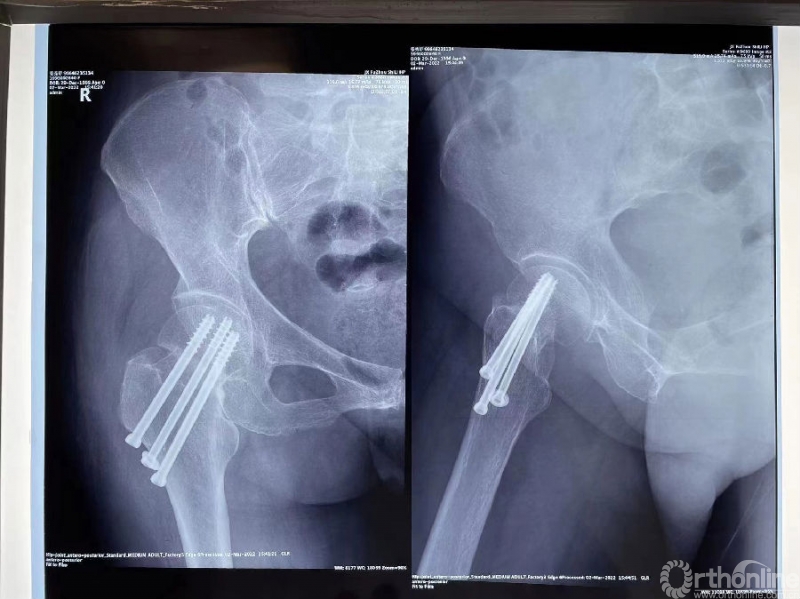

影像学资料

诊断:股骨颈基底部骨折(Garden III)并转子间骨折

初次治疗:切开复位锁定钢板内固定

术后影像资料(2021.9.21)

骨折术后骨不连(2022.3)

骨折术后骨不连(2022.7.3)